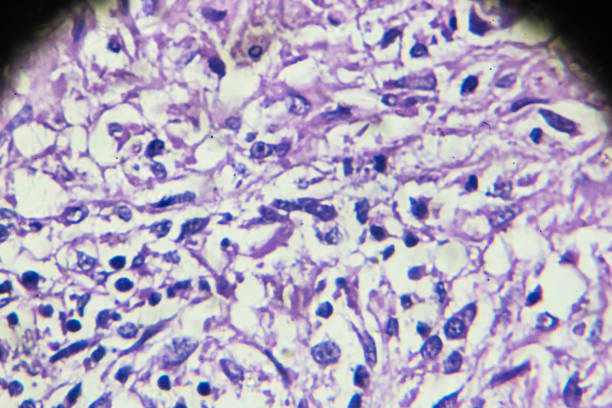

폐섬유화증은 폐조직 내 결손 및 염증에 의해 섬유화 과정이 일어나서, 건강한 폐조직이 염증과 섬유화에 대한 대체물질로 치환되는 질환입니다. 이로 인해, 섬유화된 조직은 신축성이 없고, 호흡기능이 저하됩니다. 따라서 다른 질병과 마찬가지로 초기에 적절한 치료를 받는 것이 중요하기 때문에 이번 시간에는 폐섬유화로 인한 증상들에 대해 정리해보겠습니다.